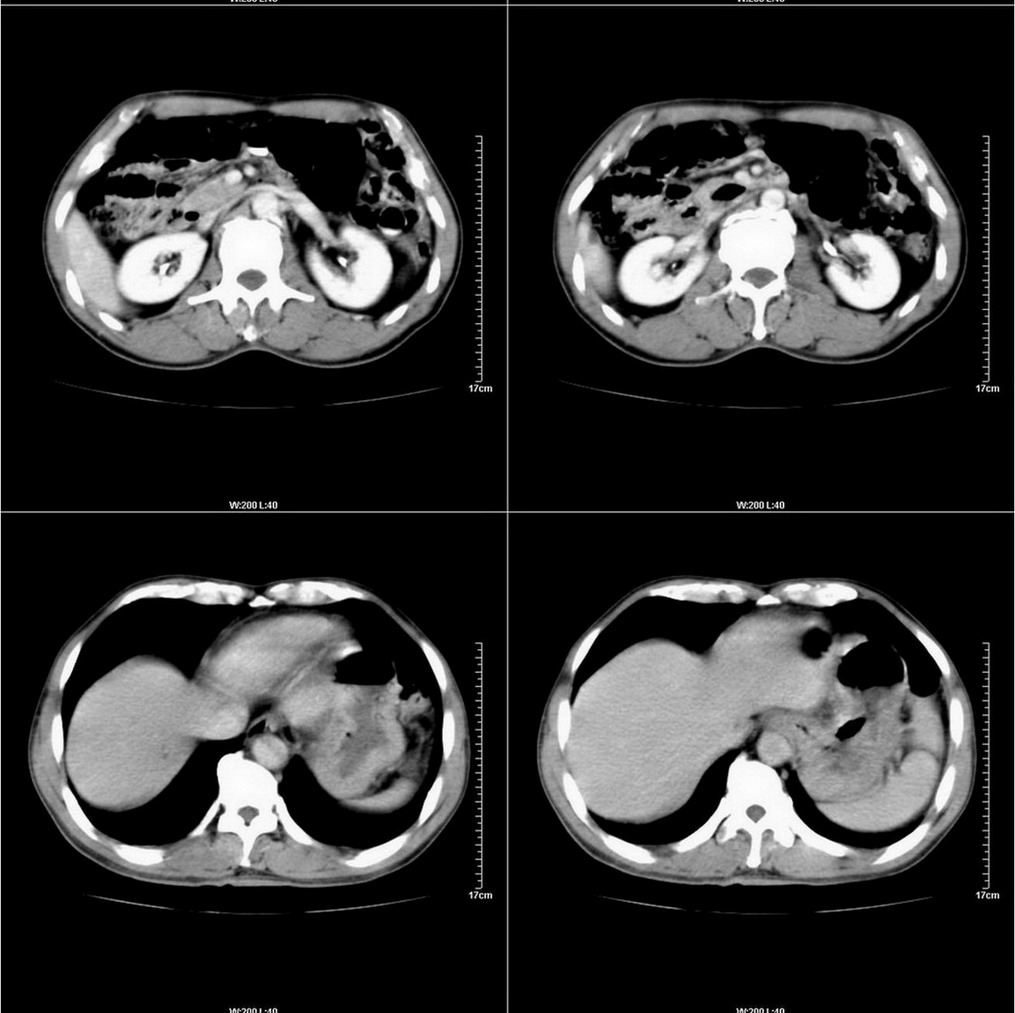

标题: CT14220:男性,59岁。腹部疼痛不适半年余。 [打印本页]

标题: CT14220:男性,59岁。腹部疼痛不适半年余。

胃壁弥漫增后,考虑胃炎溃疡

建议结合胃镜或钡餐检查,考虑胃底贲门癌可能性大。

肝右叶5段小囊肿。

肝右叶占位(囊肿?小肝癌?).

考虑:1、肝右叶下部小囊肿;

2、胃可能为准备充盈不良所致,必要时请胃镜进一步检查。